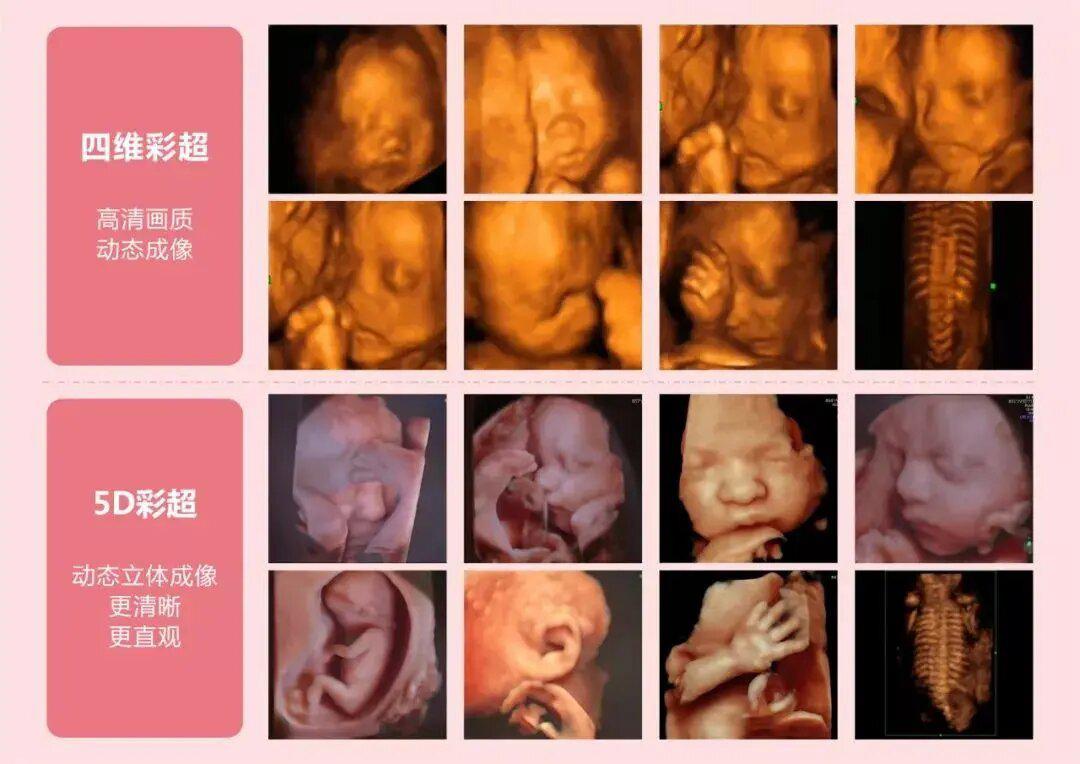

除了四维彩超,近年来五维彩超也逐渐出现,并开始被应用到临床中。洛阳白马医院也紧跟时代发展步伐,斥资引进了5D智能彩超系统。五维彩超相比于四维彩超在图像分辨率和三维实时成像等方面有了更大的突破。它可以提供更高质量的图像,并捕捉到更细节的细微变化。这使得医生能够更加准确地评估胎儿的发育情况,提前发现并处理潜在的问题。